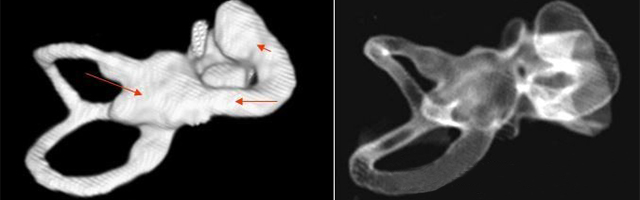

主要根據聽力學表現和影像學檢查。通過高分辨CT可看到耳蝸畸形。內耳MRI顯示膜迷路內水充盈,耳蝸扁平,耳蝸第二圈與頂圈間隔缺損,以及半規管、前庭的畸形。

先天性耳蝸畸形伴前庭和外半規管發育不良